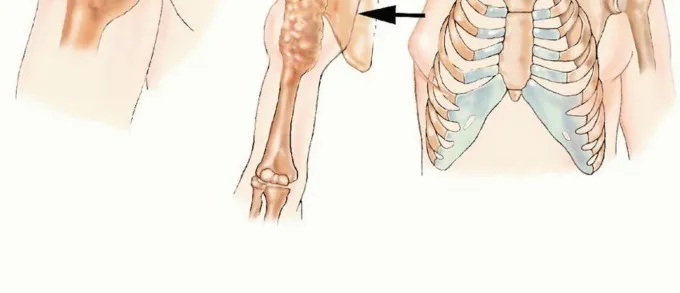

يُعد بتر الربع الأمامي (Forequarter Amputation)، والمعروف طبياً وعلمياً باسم الاستئصال الكتفي الصدري (Scapulothoracic Amputation)، أحد أكثر الإجراءات الجراحية تعقيداً في تخصص جراحة العظام والأورام. يتضمن هذا التدخل الجراحي الجذري إزالة الطرف العلوي بأكمله، بما في ذلك عظم الترقوة (Clavicle)، ولوح الكتف (Scapula)، بالإضافة إلى جميع العضلات، والأعصاب، والأوعية الدموية، والأنسجة الرخوة التي تربط الطرف العلوي بجذع الإنسان.

لفهم مدى تعقيد بتر الربع الأمامي، يجب أن نلقي نظرة عميقة على التشريح الهيكلي والوعائي والعصبي لمنطقة حزام الكتف (Shoulder Girdle). لا يقتصر هذا الإجراء على قطع العظم، بل يتطلب إعادة هيكلة كاملة لجدار الصدر الجانبي.

يتكون حزام الكتف من الترقوة في الأمام ولوح الكتف في الخلف، وهما يرتبطان بالقفص الصدري والعمود الفقري عبر شبكة معقدة من العضلات القوية (مثل العضلة الصدرية الكبرى، والعضلة الظهرية العريضة، والعضلة شبه المنحرفة). يمر عبر هذه المنطقة الحساسة:

عند إجراء بتر الربع الأمامي، يقوم الجراح بقطع وإغلاق هذه الأوعية الدموية الكبيرة بأمان شديد لمنع النزيف المميت، كما يتم قطع الأعصاب بطريقة تقلل من خطر الإصابة بآلام الطرف الوهمي (Phantom Limb Pain) المبرحة مستقبلاً. إزالة لوح الكتف والترقوة تعني تغيير شكل الجذع بشكل دائم، مما يبرز أهمية إعادة التأهيل الجسدي والنفسي لاحقاً.

الخطوة الأولى: التخطيط والشق الجراحي

يبدأ الجراح برسم الشق الجراحي على شكل "مضرب التنس" (Racquet-shaped incision). يبدأ الشق من أعلى الكتف (منطقة الترقوة)، ويمتد حول الإبط، ثم ينزل على طول جدار الصدر والظهر. يتم تصميم الشق بطريقة تضمن ترك سديلة جلدية وعضلية (Flap) كافية لتغطية الجرح الكبير لاحقاً.

الخطوة الرابعة: قطع العظام وفصل العضلات

يتم استخدام منشار جراحي لقطع عظم الترقوة من منتصفه أو من مفصله مع عظم القص. بعد ذلك، يتم فصل العضلات التي تربط لوح الكتف بالقفص الصدري والعمود الفقري (مثل العضلة المنشارية الأمامية، والعضلة الظهرية العريضة). بمجرد فصل جميع هذه الهياكل، يتم إزالة الطرف العلوي بالكامل ككتلة واحدة (En bloc resection) لضمان عدم ترك أي خلايا سرطانية.